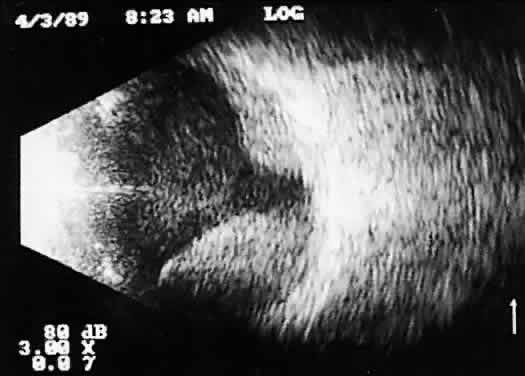

Real time refers to the display of motion or movement during B-scan imaging. This capability is one of the greatest advantages of B-scan. Differences in mobility of a variety of movable intraocular abnormalities can be easily detected. For example, the rapid movement of vitreous hemorrhage is usually easy to appreciate and differentiate from the slower, undulating movements of a recent, rhegmatogenous retinal detachment. On occasion, movement of intraocular structures can be used for detecting abnormalities that lie immediately behind vitreous opacification and may be seen only when the vitreous opacities are moved away from the ocular wall, set in motion by command voluntary movements of the patient's globe (Fig. 5). Gray scale refers to the variable gray tone of display screen echoes. Strong returning signals (echoes) appear white, whereas weaker reflections are seen as gray, the shade depending on echo strength. Examples of strong reflectors of sound include retinal tissue, sclera, and calcifications of any type (Fig. 6). Weaker echoes from clotted or clumped cells within the vitreous are usually easy to differentiate from the stronger reflectors of sound (Fig. 7). Grading of echo strength may be performed only when the examining ultrasound beam is perpendicular to the object of interest, ensuring the strongest possible reflections. However, in the world of ultrasound interpretation, there are many exception to the rules. Tissues that are usually mild reflectors of sound, such as hemorrhage, can at times appear quite strong, especially in complex or multiple pattern disorders, as frequently occur in severe ocular trauma. These apparent inconsistencies often cause misinterpretation by the novice. With experience obtained by multiple examinations, careful follow-up, and clinical correlation whenever possible, diagnostic acumen rapidly improves.

Fig. 7. Contact B-scan. Clotted or clumped cells, such as those seen in mild vitreous hemorrhage, appear pale gray.